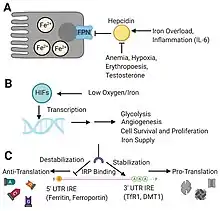

Cigarettes contain a small amount of iron, but cumulatively a larger quantity in daily smoking.[13] The increasing iron exposure in the lung and airway affects both respiratory and systemic iron homeostasis by modifying cellular response. Although direct etiologic link has not been established, there is a 4-fold increase in intracellular iron level and a concomitant iron release observed in smoker’s macrophage.[4][13] While iron-loading affects macrophage activation and functions, excessive extracellular iron favors bacterial growth. Normally, activated alveolar macrophage secretes lipocalin-2 which traps bacterial siderophores and prevents bacterial iron uptake. Iron imbalance locally in the lung thus results in higher risk of infection.

Hemosiderin is the iron storage in smoker's macrophage rather than ferritin. It is formed during hemorrhage or abnormal metabolism of ferritin.[14][15] Indeed, buildup of iron causes oxidative stress resulting in lung damage and mitochondrial dysfunction.[13] The level of hemosiderin-laden macrophage is also associated with pulmonary hemodynamics parameters which is used to evaluate pulmonary hypertension in the early stage of diseases.[16]

Iron homeostasis has been associated with macrophage polarization and reprogramming despite unclear causality in cigarette iron.[13] M1 macrophage demonstrates high TF, HAMP, and FTH1 gene activities that mediates iron uptake. M2 macrophage on the other hand expresses FPN1 which causes iron release. Supplementing iron to mice predisposes macrophage to M2 phenotype and inhibits M1-mediated inflammation.